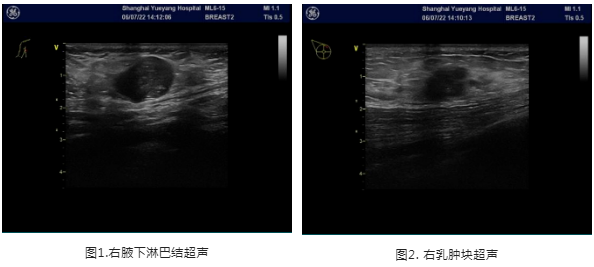

2021年6月8日乳房超声:右乳内见数个低回声区,较大者1点位20x10x18mm,边界欠清,形态欠规则,内见点状强回声,内见血流信号腋下:右侧见数个低回声区,较大者21x13mm,淋巴门结构不清晰,内见血流信号;

结论:右乳结节,BI-RADS 4B;右侧腋下淋巴结肿大

▌穿刺病理

2022.06.07患者于我院行右乳肿块及右腋下肿大淋巴结空芯针穿刺活检术,穿刺病理病理:1.(右乳肿块穿刺)浸润性癌。2.(右侧腋窝淋巴结穿刺)见癌转移,首先考虑乳腺转移来源;